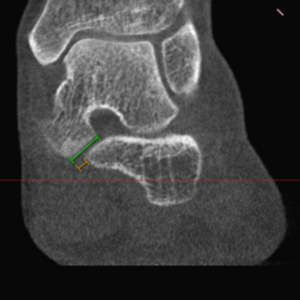

WBCT is a transformative imaging technology that captures accurate 3D measurements of the lower limb in a natural weight-bearing stance. At GRAV-ET, WBCT is central to our research, enabling precise assessment of alignment and deformity. Our lab utilizes the CurveBeamAI HiRise scanner, which provides comprehensive lower-limb imaging from toe tips to hips, supporting advanced modeling and surgical planning.

Advanced Visualization

Advanced visualization enhances the diagnostic capabilities of WBCT combined with sophisticated 3D techniques in Computer Science to offer new insights into bone and joint physiology and pathology. Techniques such as Artificial Intelligence (AI) and Machine Learning (ML) are utilized. The Grav-ET lab is equipped with Disior software (https://www.disior.com/), which provides the research team with segmentation and advanced visualization tools, including distance measurement, coverage mapping, and automated 3D measurements. Hounsfield Unit (HU) analysis allows the study of local variations in Bone Mineral Density (BMD), named after Sir Godfrey Hounsfield, Nobel Prize winner for the invention of CT.